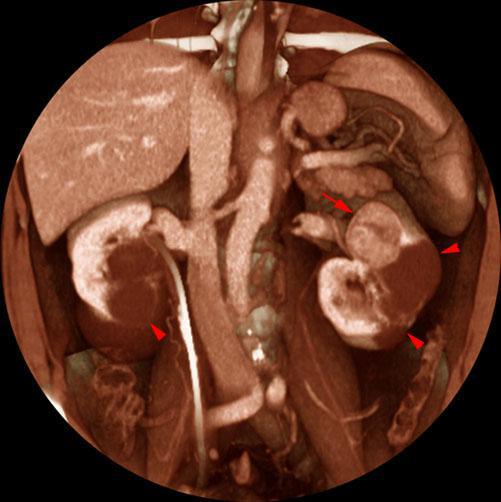

Quiste renal multitabicado e hipernefroma